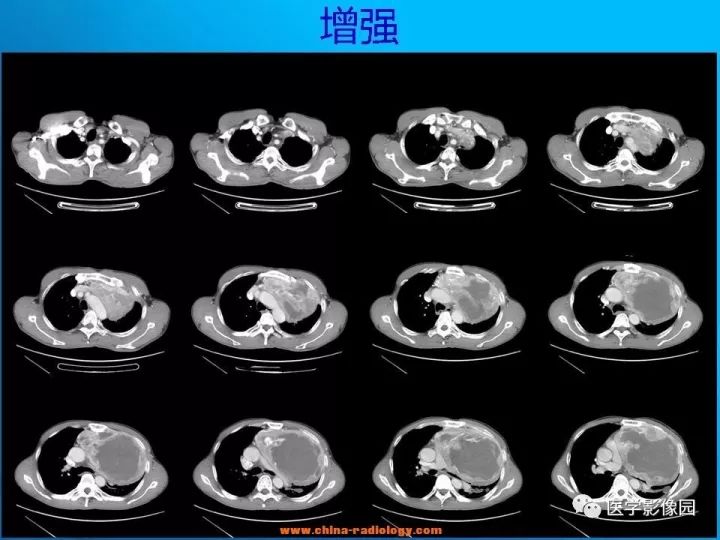

CT表现

1.肿瘤多为单发,平扫密度略低于肌肉,轮廓光整,呈类圆形或卵圆形,肿瘤较大时可为不规则形或呈分叶状,易囊变,常为囊实性,有包膜,可有钙化。

2.增强扫描多数病例肿瘤强化轻微,包膜可强化,少数病例可有较明显强化。

3.当肿块体积较大,并向周围侵犯,其内密度混杂,尤其是囊变、坏死明显;实性部分呈斑片状及网格状较明显强化;往往提示为恶性神经鞘瘤。